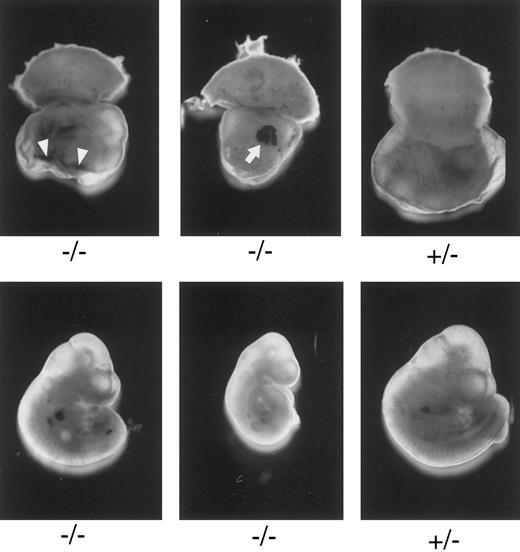

Macroscopic examination of E10.3 embryos. TFPIK1 genotypes are indicated. Arrowheads, intra-yolk sac hemorrhage with red blood cells in yolk sac folds; arrow, blood “lakes” in yolk sac. Note that yolk sac hemorrhage can be found with a near normal embryo (left, bottom), suggesting that hemorrhage and concomitant circulatory collapse precede the wasting and ultimate death of the embryo.

Characterization of TFPIK1(−/−) mice.Of 233 pups born following the mating of heterozygotic TFPIK1(+/−) mice, 35% were TFPIK1(+/+) and 65% were TFPIK1(+/−) (Table 1). To examine the phenotype of TFPIK1(−/−) mice, embryos were collected at various times of gestation after matings between TFPIK1(+/−) mice. TFPIK1(−/−) embryos were indistinguishable from TFPIK1(+/−) and TFPIK1(+/+) at embryonic day 8.5 (E8.5) (data not shown). Between E9.5 and E11.5, however, many of the TFPIK1(−/−) concepti displayed intra-yolk sac hemorrhage and a paucity of blood in yolk sac vessels (Fig 2). The embryos contained within these yolk sacs were usually pale and growth retarded, and occasionally had pericardial effusions containing extravasated red blood cells.